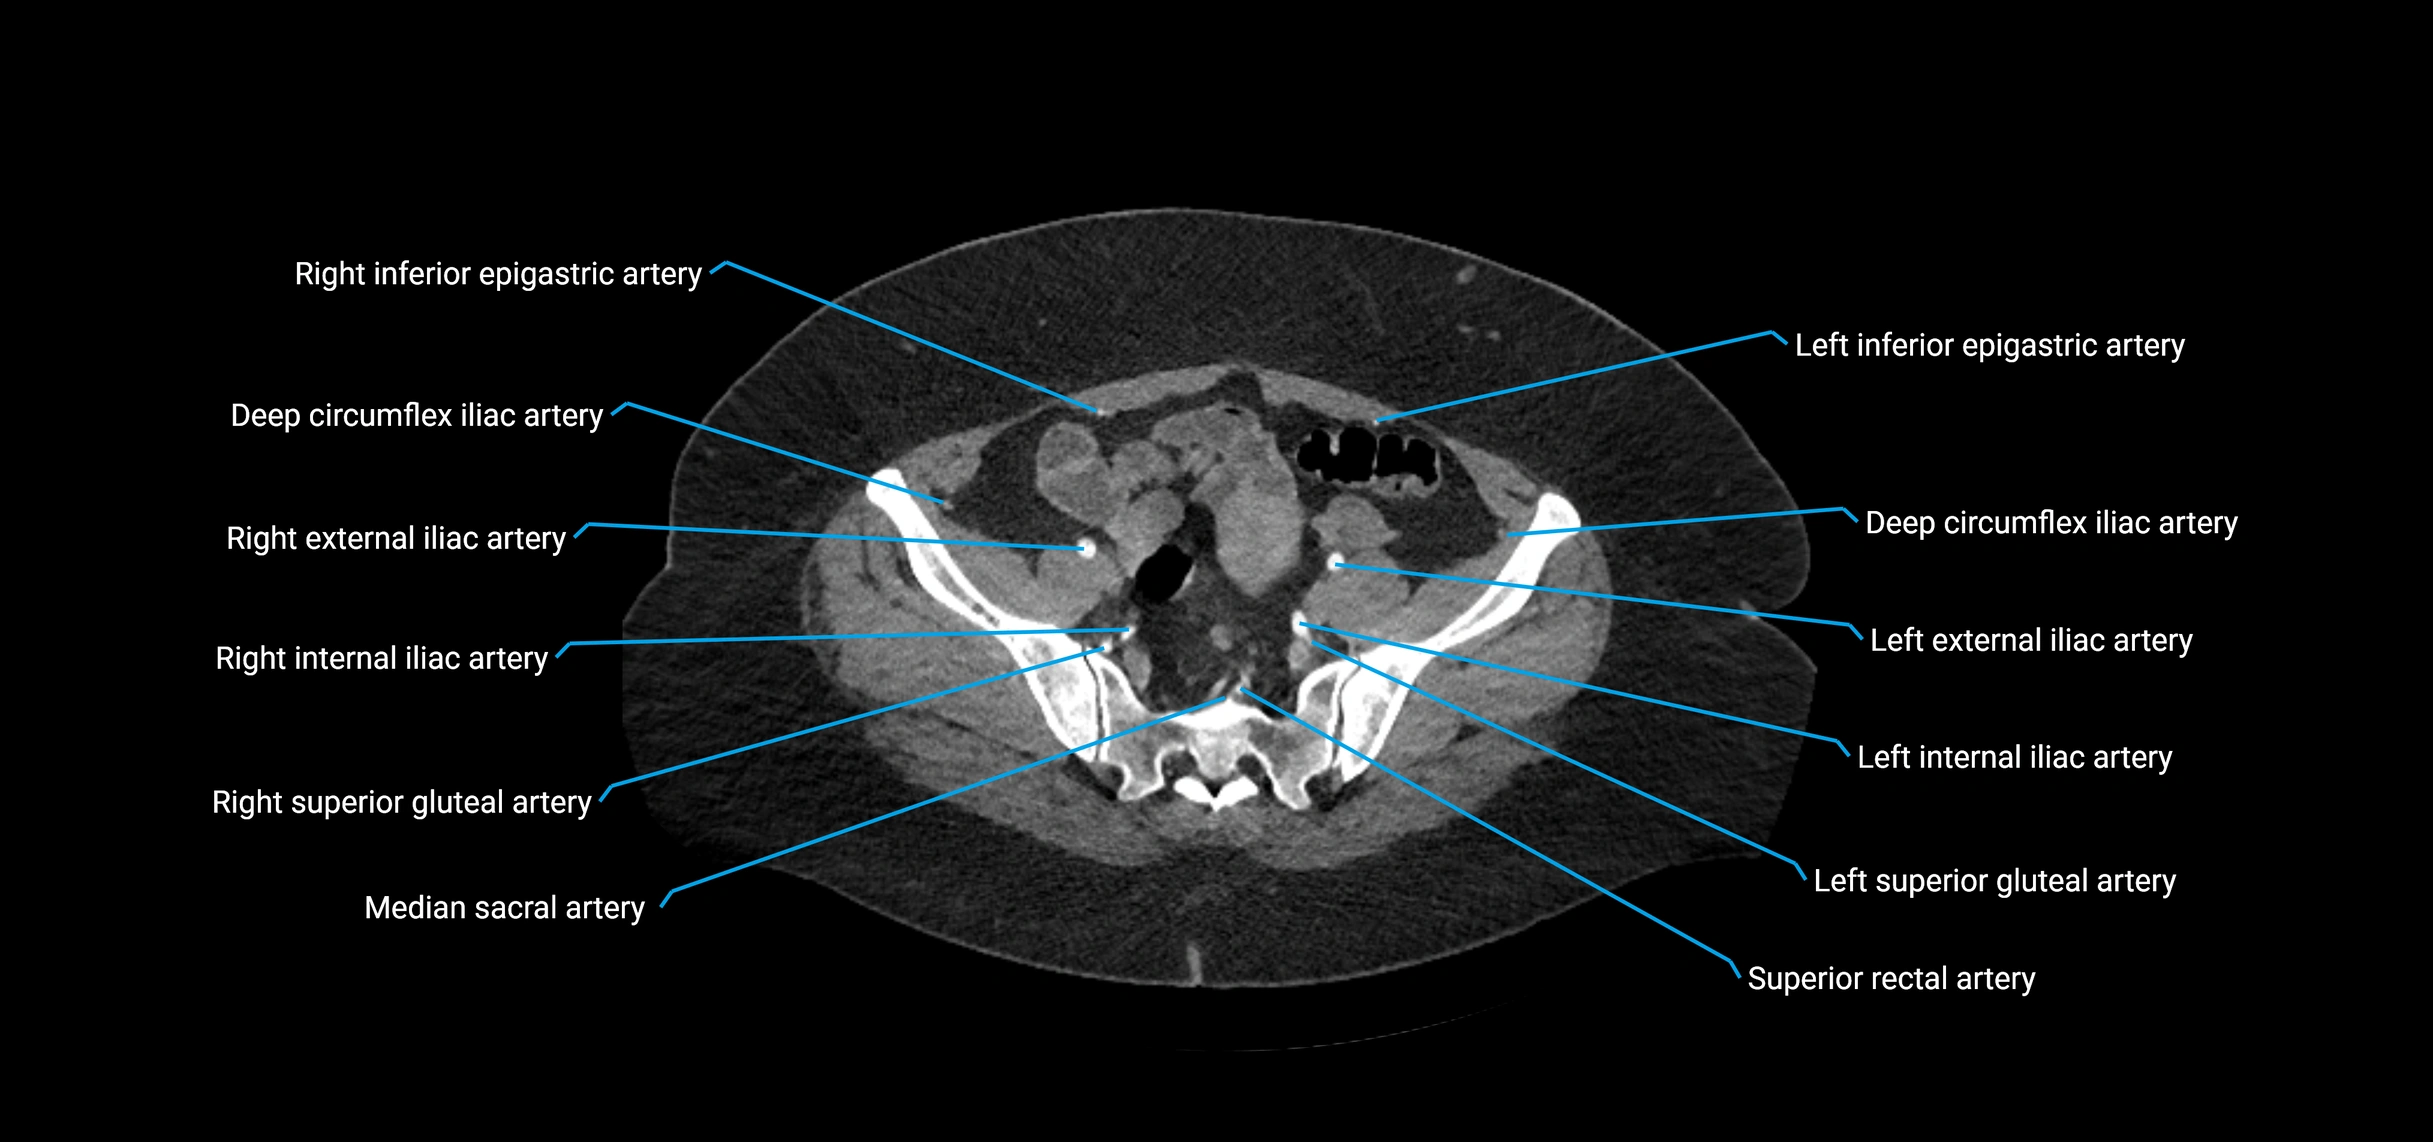

Contrast-enhanced CT (CTA):

• Gold standard for abdominal aortic imaging

• Provides excellent detail of lumen, wall, aneurysm, thrombus, and branch vessels

• Multiplanar and 3D reconstructions help in aneurysm measurement, stent graft planning, and dissection evaluation

• Detects acute rupture, traumatic injury, or occlusion with high sensitivity